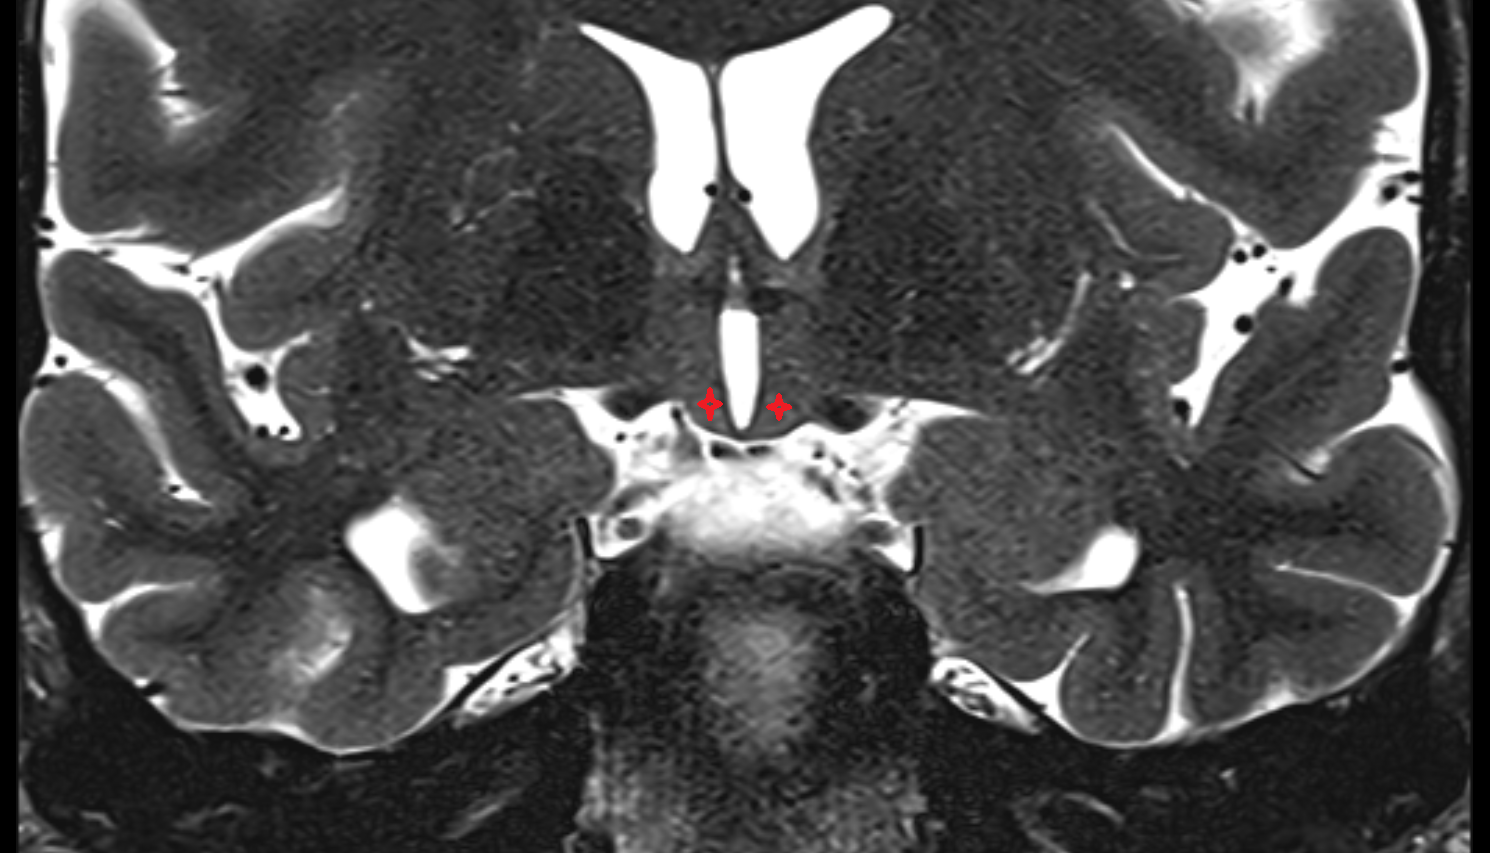

- Hippocampus